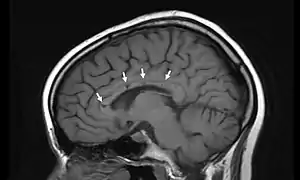

| Sagittal T1 image in a 19-year-old woman with Susac's syndrome showing the pathognomonic central callosal "holes" (microinfarcts) of SS. These residual "holes" (and sometimes, "spokes") develop as the acute callosal changes resolve. | |

In a recent analysis (Susac et al., 2003), MRI images from 27 patients fulfilling the diagnostic criteria of Susac's syndrome were reviewed. Multifocal supratentorial lesions were present in all patients. Most lesions were small (3 to 7 mm), though some were larger than 7 mm. All 27 patients had corpus callosum lesions. These all had a punched-out appearance on follow up MRI. Though most commonly involving white matter, many patients also had lesions in deep grey matter structures, as well as leptomeningeal enhancement. Multiple sclerosis (MS) and acute disseminated encephalomyelitis (ADEM) can mimic the MRI changes seen in patients with Susac's syndrome. However, the callosal lesions in Susac's syndrome are centrally located. In comparison, patients with MS and ADEM typically have lesions involving the undersurface of the corpus callosum. Deep gray matter involvement commonly occurs in ADEM but is very rare in MS. Leptomeningeal involvement is not typical of either MS or ADEM. What this means is that if 10 lesions are found in the brain of an MS patient, a lesion may be found in the corpus callosum. If you have 10 lesions in a Susac patient, more than half will be in the corpus callosum.